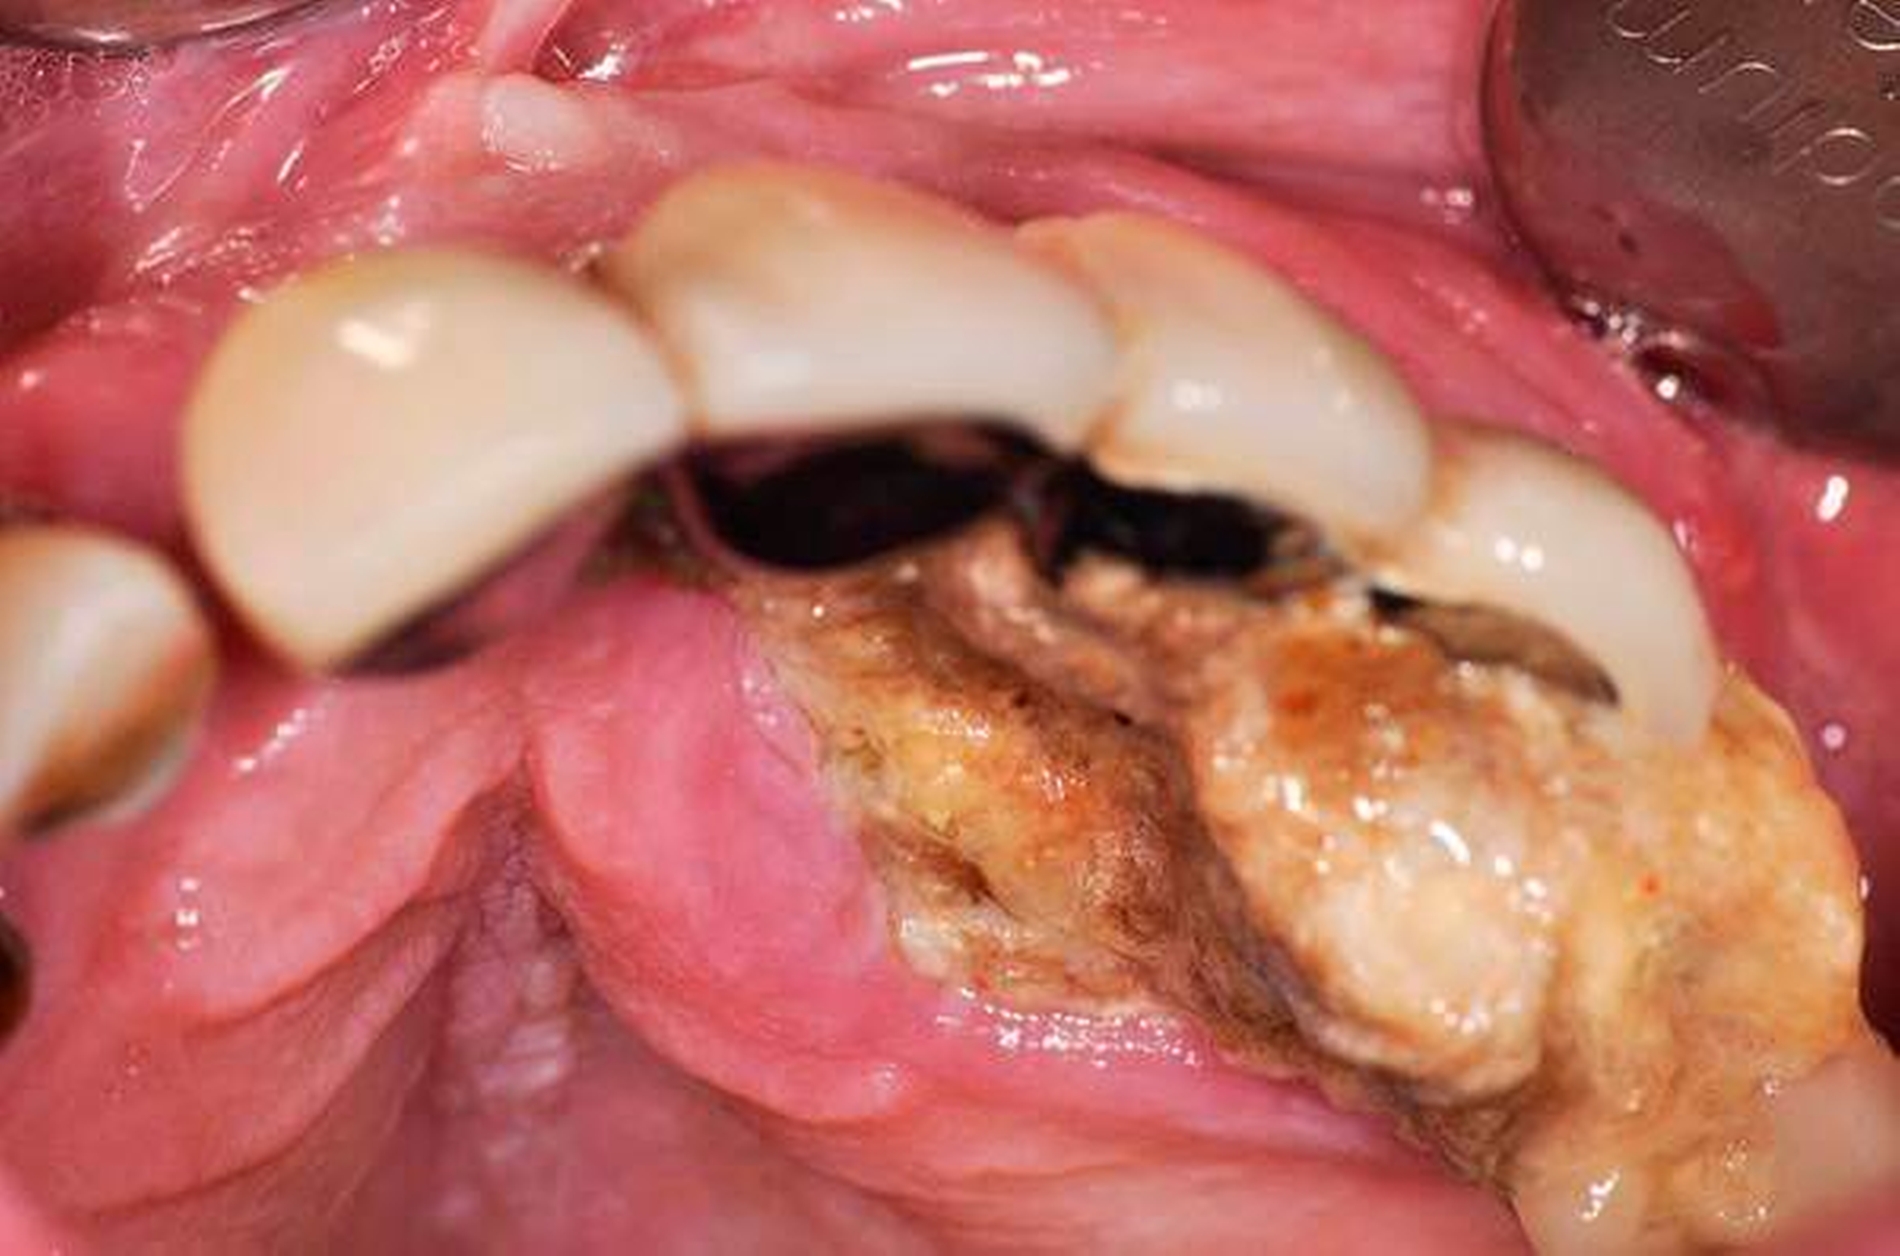

Bei Druckschmerzhaftigkeit im linken Oberkiefer und dort lokalisierter, stark gelockerter Brücke erfolgte die Überweisung des Patienten an die Abteilung für Mund-, Kiefer- und plastische Gesichtschirurgie der Universitätsmedizin Mainz. Klinisch stellte sich der Befund als druckschmerzhafte Strukturveränderung des Hartgewebes unterhalb der maxillär lokalisierten Brücke im rechten Oberkiefer bei drittgradig gelockerter Restbezahnung und insgesamt schlechter Mundhygiene dar (Abbildungen 1 und 2).

In der durchgeführten radiologischen Diagnostik zeigten sich ausgeprägte Parodontopathien mit Verdacht auf eine BRONJ bei gut begrenzter radiologischer Aufhellung mit Kieferhöhlenbeteilung (Abbildungen 3 bis 5). Unter der Verdachtsdiagnose einer BRONJ wurde somit die Indikation zur Zahnsanierung mit Exzision der pathologischen Veränderung im Oberkiefer gestellt. Nach Entfernung der gelockerten Brücke zusammen mit den die Brücke tragenden Zähnen zeigten sich große Mengen harten, anhaftenden Gewebes (Abbildung 6); der unter dem Befund liegende Knochen stellte sich klinisch als vital und ohne Anzeichen einer Nekrose dar.